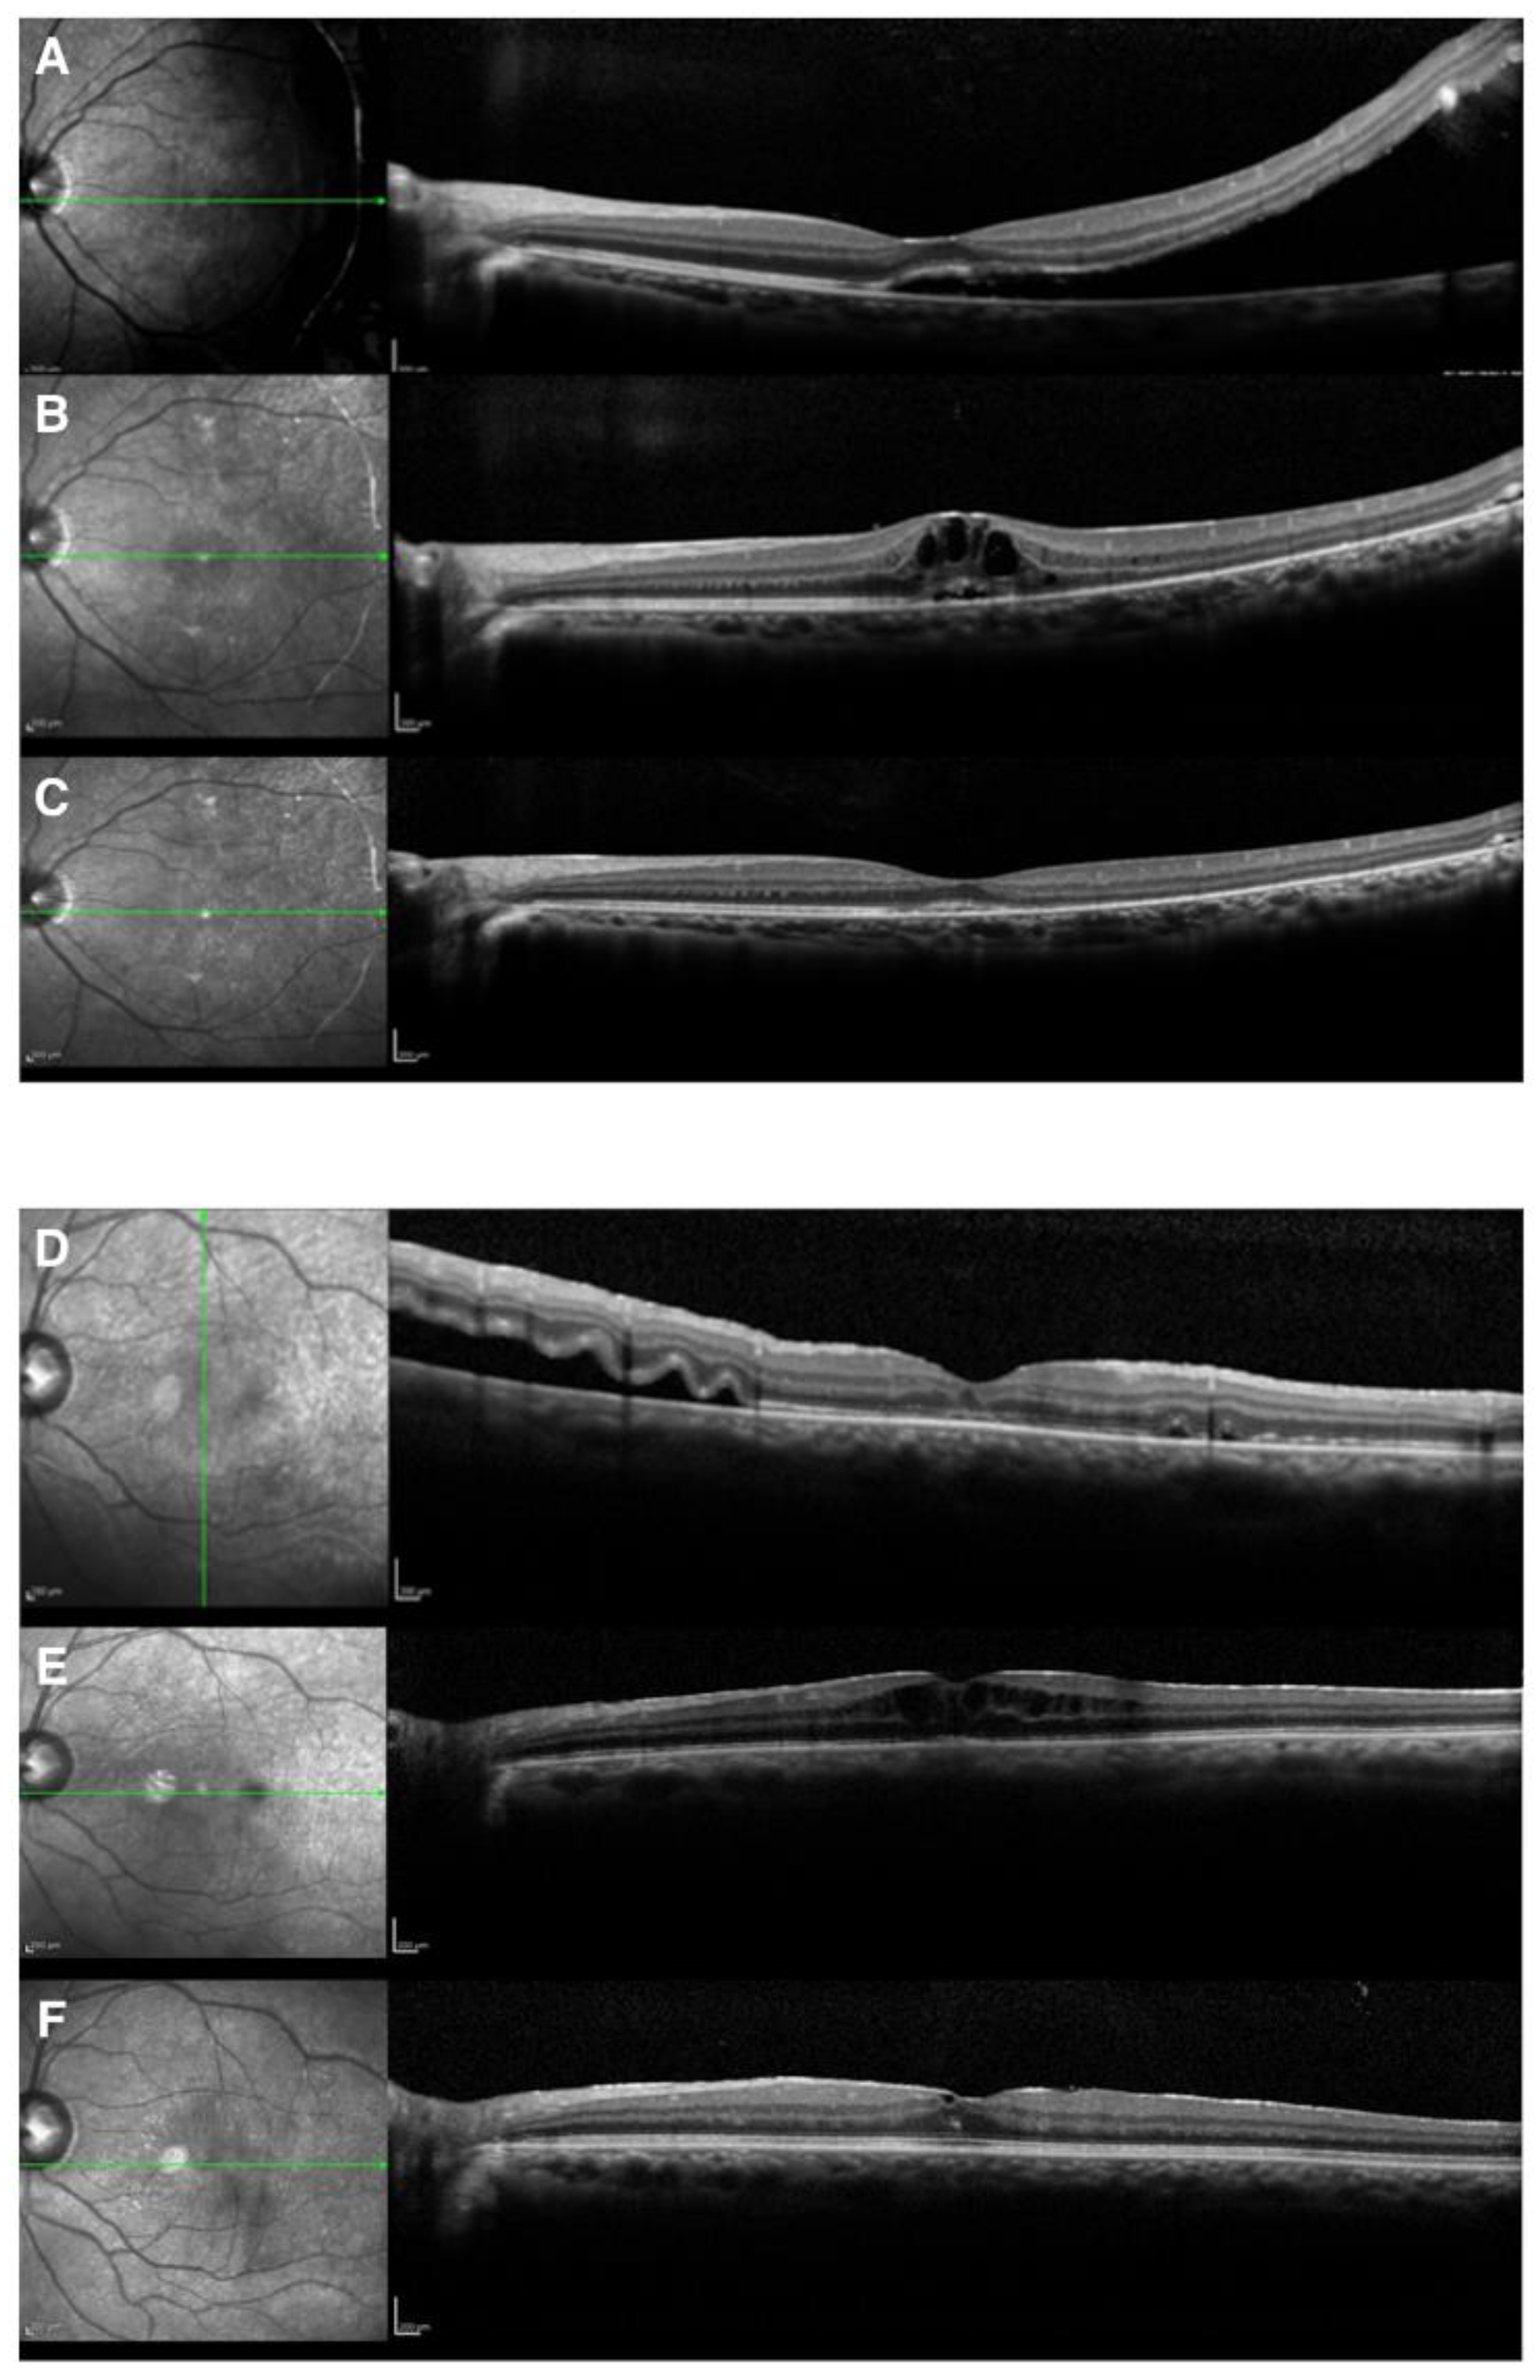

CME occurred in six (2.2%) eyes in six patients, none of whom had diabetes. Regarding the lens status, 3 of 247 phakic eyes (1.2%) and 3 of 24 (12.5%) pseudophakic and aphakic eyes developed CME (chi-squared, p = 0.0078) (Table 2). The detailed clinical characteristics are shown in Table 3, while images of two representative cases are shown in Figure 2. There were no significant differences in other factors, including the macular status, SRF drainage, air tamponade, or the performance of encircling and laser in situ keratomileusis (LASIK) (all p > 0.05). Furthermore, there were no significant differences in the number of breaks, extent of retinal breaks, or extent of retinal detachment (all p > 0.05). Eyes with a history of cataract surgery appeared more likely to develop CME. Since the number of the cases with CME was low, we did not perform a multivariate regression analysis to identify predictors for CME.

Representative Cases. Case 1 was a 23-year-old woman who underwent scleral buckling surgery for RRD with a superior temporal atrophic hole associated with lattice degeneration. The fovea in her left eye was slightly detached. Subretinal drainage was not performed. The original hole was sealed on the buckle, and the subretinal fluid was gradually absorbed. CME appeared 1 month after buckling surgery. CME temporarily disappeared with oral acetazolamide. However, when internal use was withdrawn, CME recurred. Recurrent CME was observed three times in 7 months. CME disappeared completely after three recurrences. The logMAR BCVA improved from 1.22 to 0.

Case 2 was a 48-year-old-man who had undergone cataract surgery for his left eye 5 years before the appearance of retinal detachment. He underwent scleral buckling surgery for macula-off RRD due to a nasal tear in his left eye. We performed air tamponade without draining the subretinal fluid. The subretinal fluid was gradually absorbed; however, CME was observed 2 weeks after buckling surgery. The CME did not improve with acetazolamide treatment; thus, he was treated with the subtenon injection of triamcinolone acetonide and the intravitreal injection of anti-vascular endothelial growth factor. CME slightly persisted; however, the logMAR BCVA improved from 0.52 to 0.22.

Figure 2. Cases 1 and 2 are presented as representative cases. Case 1: preoperative OCT (A); postoperative CME (B); OCT at 1 year after surgery (C). Case 2: preoperative OCT (D); postoperative CME (E); OCT at 1 year after surgery (F). Both (A) and (D) showed macular detachment before surgery. As for the timing of onset of postoperative CME, (B) showed CME 1 month after surgery, and (E) showed CME 2 weeks later. CME disappeared in (C) but was found to have remained 1 year after surgery (F).